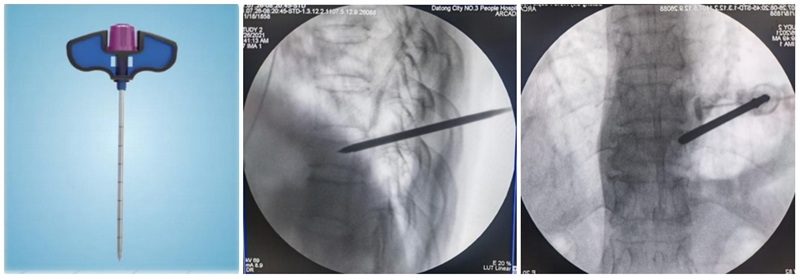

PCKP的优势在于术中操作安全、便捷、骨水泥弥散好,渗漏率低。术中穿刺过程中穿刺针以更小的穿刺角度进入椎体内,通过弯角骨钻开腔越过椎体中线,增加了穿刺安全区间,减少了术中医源性穿刺损伤的风险;同时通过弯角球囊的独特设计,可以在椎体中部造成弧形空腔,引导骨水泥在灌注过程中从穿刺对侧开始弥散,沿球囊撑开的弧形空腔充分灌注,达到单侧穿刺、双侧弥散的效果,有效降低了骨水泥渗漏风险。

(1)定位与穿刺:透视下确定伤椎椎弓根外缘上1/3 入路点及伤椎上终板或下终板方向并做好标记。由于穿刺容错率高,穿刺针(4. 2 mm)不用过度内倾,不必苛求针尖在椎体内侧壁、后壁位置,穿刺针从椎弓根外缘沿椎弓根方向缓慢穿刺入椎体即可,针尖务必穿刺入椎体后1/3。

(2)弯角导丝开腔:弯角骨钻开腔器械刺入椎体时,注意开腔工具手柄与伤椎终板平行,不要强行开腔,多透视侧位,否则弯导丝可能穿破终板,导致医源性骨水泥渗漏。C形臂X线机正位透视下,导丝到达椎体对侧椎弓根处即可。

(3)弯角骨钻扩张:C形臂X线机正位透视下,弯角骨钻开腔器械螺旋手柄顺时针扭转,让弯角骨钻沿导丝前进开路,将椎体内部钻出弧形通道。操作中注意骨钻沿导丝旋进旋出要完全,旋进不够,后期球囊无法到达对侧,旋出不完全,骨钻会卡在工作套筒上无法拔出。

(4)置入球囊:插入带导丝弯角球囊时注意透视球囊方向,反复调整务必与终板平行。如需要拔出球囊调整方向,务必先拔导丝再拔球囊,透视球囊标记点必须完全从工作套管内出来,否则易造成弯角球囊与工作套管边缘卡磨破裂。

(5)扩张球囊:注入造影剂扩张球囊过程中,注意观察术中正侧位透视图像,控制压力值,不必苛求球囊顶到上下终板,以免发生医源性终板破裂,造成椎间隙骨水泥渗漏可能。注意弯角球囊扩张完毕后拔除顺序:先拔导丝再拔球囊。

(6)注入骨水泥:应用骨水泥灌注管灌注骨水泥时,由聚醚醚酮树脂制成的灌注管在骨水泥灌注完成后要及时拔除,避免椎体内骨水泥硬化后无法拔出;椎体穿刺侧骨水泥灌注不满意,可拔除输送套管,直接连接穿刺套管,进行二次灌注。

术后行影像学检查,显示骨水泥弥散满意,达到了单侧穿刺,双侧弥散的效果,无渗漏